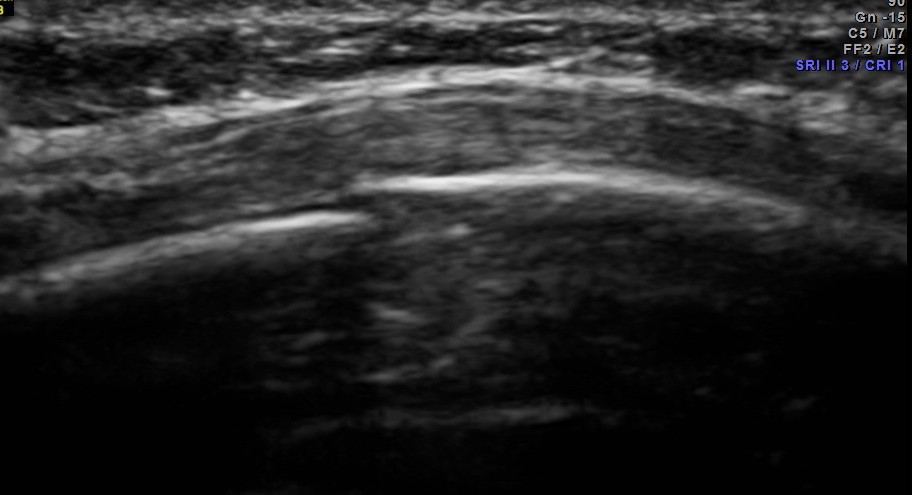

This was a 25 year old lady who fell on her chest while a cow was chasing her . She had persistent severe pain in the left side of the chest. Xray of the rib cage was reported as normal and appeared to be normal.

Scan over the point of maximal tenderness ( over the 6th rib on the left side anteriorly) revealed a crack in the bone on the posterior aspect . Probably as it was not a complete fracture it was missed on the xray.

The images are shown below